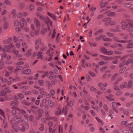

To deal with some of the aforementioned issues, we introduce a new approach for simultaneous H&E stain normalization and augmentation based on the multimarginal Wasserstein barycenter approach. Specifically, the novelty of the paper lies in first introducing the traditional Wasserstein barycenter approach for stain normalization/augmentation (Figure 1), and then introducing the multimarginal version [1, 9] to overcome the limitations of the traditional approach in this context (Figure 2). Note that the traditional Wasserstein barycenter (1 source and 1 reference), although widely employed in computer vision, to the best of our knowledge has never been used for stain normalization/augmentation and the more general multimarginal Wasserstein barycenter (1 source and multiple references) has hardly ever been used in computer vision or medical imaging communities. For more accurate stain normalization, the multimarginal version allows one to incorporate additional distributions by utilizing one or more intermediate reference images (Figure 2). The resultant interpolations span a broad spectrum of stain variations allowing for simultaneous stain normalization and augmentation.

We used MITOS-ATYPIA’14 challenge dataset for evaluating our stain normalization. The dataset includes same tissue sections scanned by two different scanners (Aperio-A and Hamamatsu-H) with total 424 X20 A-H frame pairs, 300 training and 124 testing. Images from scanner A are normalized and matched against the real corresponding images from H (ground truth). As in StainGAN [14], 10,000 random (256256) patches from 300 training frames were used for training (26 epochs with the regularization parameter , learning rate 0.0002, Adam optimizer with a batch size of 4) and 500 patches from 124 testing data used for evaluation. The visual and quantitative comparisons are shown in Figure 3 and Table 1, respectively. For the traditional case (one reference and source), our results are very similar to Reinhard et al. [12] since they also do color matching in Lab space, but our results improve drastically given two reference images. The references in our case span patches with different amounts of background visible. We also tested with different reference images and we show that we get a tighter bound as long as the references contain different amounts of background visibility; see Figure 4 for the box plots of SSIM for different references.